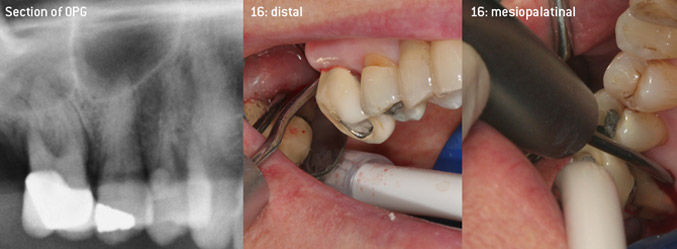

As initiators of the development of the new diamond-coated 3AP air scaler tip, the two dentists recognized the need for improvement of the handling restrictions of the commercially available diamond-coated tips, especially during furcation treatment and when working in tight intraosseous pockets. This should be possible for both non-surgical (Figure 2) and surgical (Figure 3) procedures.

Open debridement of the furcations on teeth 16 and 17

Fig. 3: Open debridement of the furcations on teeth 16 and 17 in case of advanced attachment loss

The aim was to develop a universally applicable tip in order to avoid time-consuming tip changes. In addition, it should be easier to use the new working tips in tight intraosseous pockets from distal and at the distal furcation entrance of maxillary molars, allowing more effective use of instruments as a result. This was achieved by employing an instrument curve with a larger diameter (Figure 1), which is highly advantageous for closed debridement on teeth with advanced attachment loss and involvement of furcation in particular (Figure 4).

Closed debridement of the furcation on tooth 16

Fig. 4: Closed debridement of the furcation on tooth 16 with advanced attachment loss